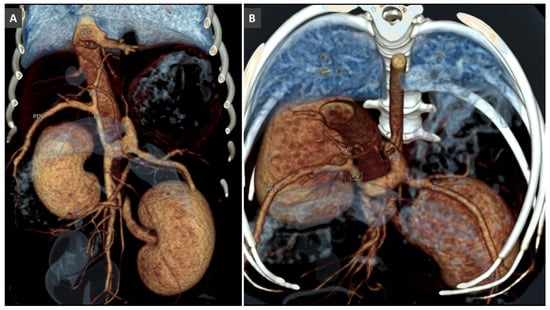

3.5. Anomalous Vascular Connections of the Portal Vein System

High-Flow Anomalous Portal Connections

3.8. Porto-Portal Collaterals or Cavernous Transformation of the Portal Vein